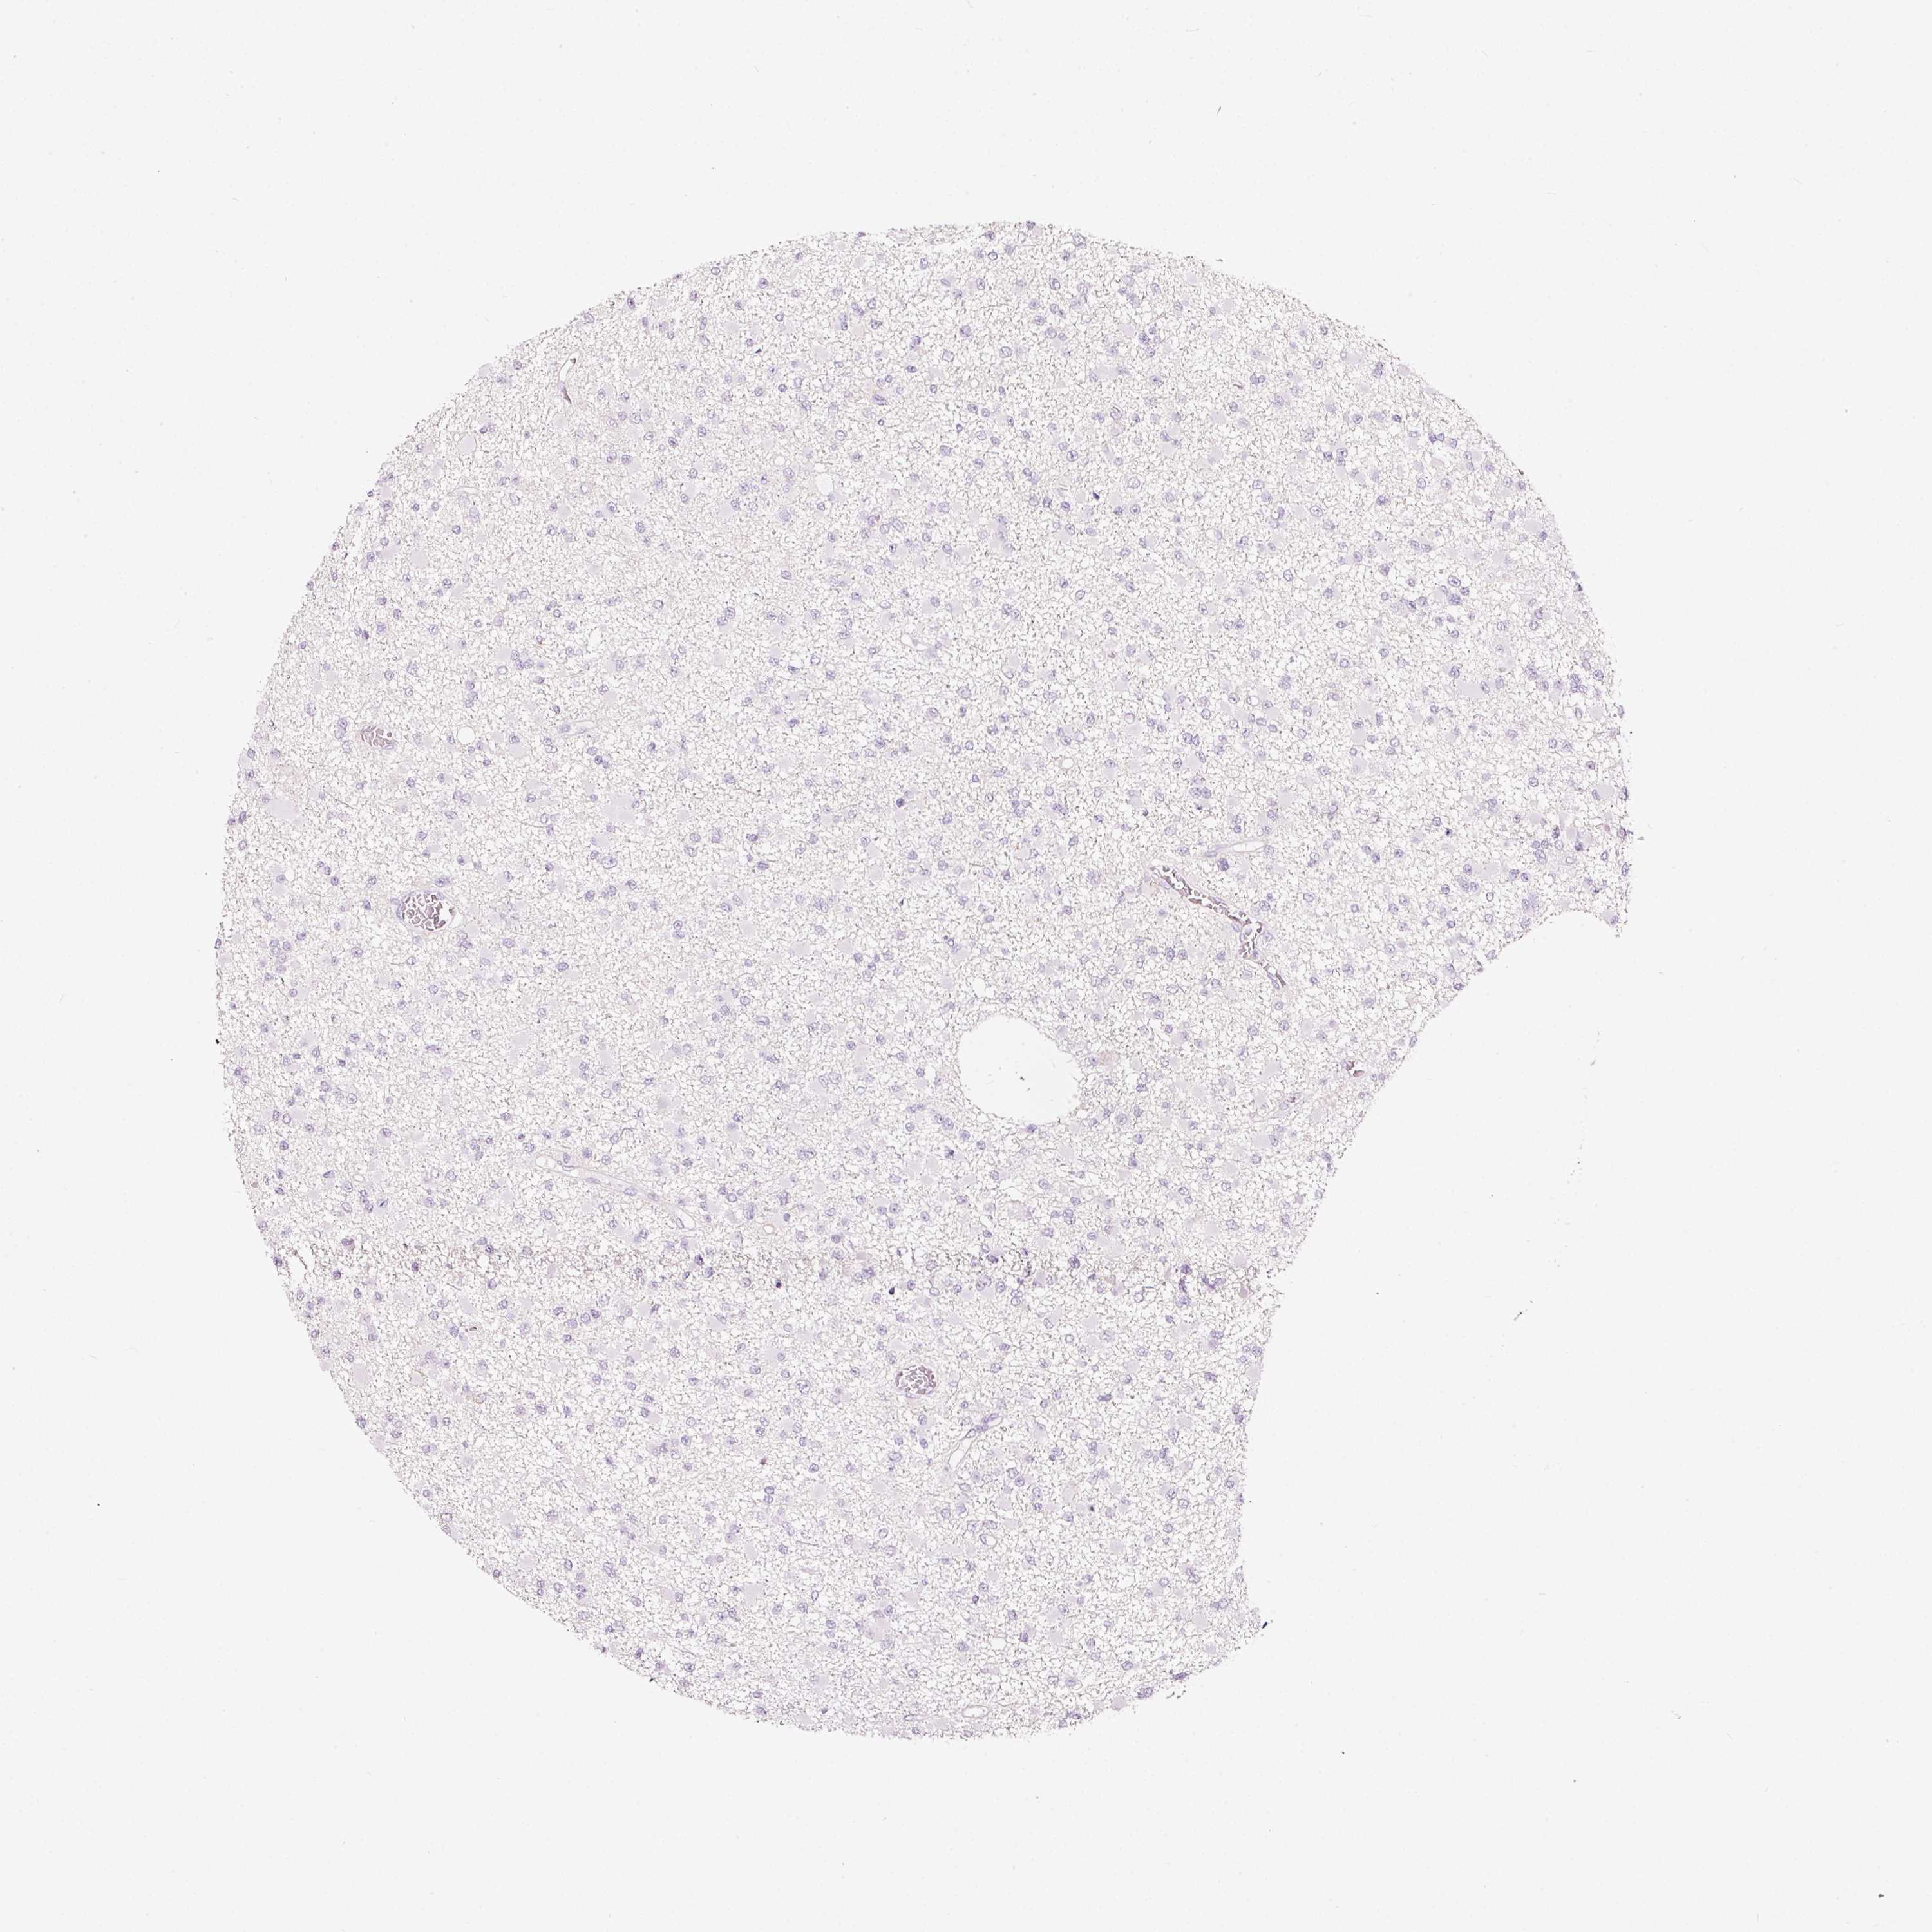

GLIOMA - Protein expressioni

A mouse-over function shows sample information and annotation data. Click on an image to view it in a full screen mode. Samples can be filtered based on level of antibody staining by selecting one or several of the following categories: high, medium, low and not detected. The assay and annotation is described here.

Note that samples used for immunohistochemistry by the Human Protein Atlas do not correspond to samples in the TCGA dataset.

Antibody stainingi

Antibody staining in the annotated cell types in the current human tissue is reported as not detected, low, medium, or high, based on conventional immunohistochemistry profiling in selected tissues. This score is based on the combination of the staining intensity and fraction of stained cells.

Each image is clickable and will lead to virtual microscopy that enables deeper exploration of all samples and also displays staining intensity scores, fraction scores and subcellular localization as well as patient and tissue information for each sample.

Antibody HPA051467

Antibody CAB025133

Staining

High

Medium

Low

Not detected

Intensity

Strong

Moderate

Weak

Negative

Quantity

>75%

75%-25%

<25%

None

Location

Nuclear

Cytoplasmic/membranous

Cytoplasmic/membranous,nuclear

Glioma, malignant, High grade

Glioma, malignant, Low grade